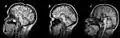

- Image du corps calleux en coupe sagittale(plan vertical, orienté d'avant en arrière) en IRM (imagerie par résonance magnétique).

IRM révélant une agénésie du corps calleux.